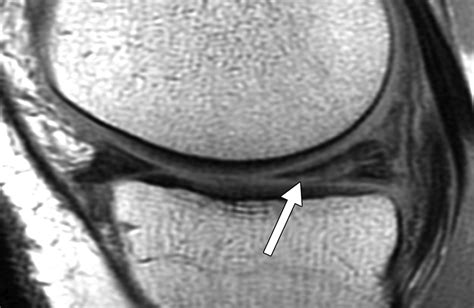

If you suspect an injury to the lateral meniscus, it is essential to consult a healthcare professional. A physical examination typically involves the McMurray test or the Apley compression test to reproduce pain and identify the location of the tear. To confirm the diagnosis and rule out other structural issues, your doctor may request specific imaging.

MRI (Magnetic Resonance Imaging) Provide detailed images of soft tissues to visualize the tear.